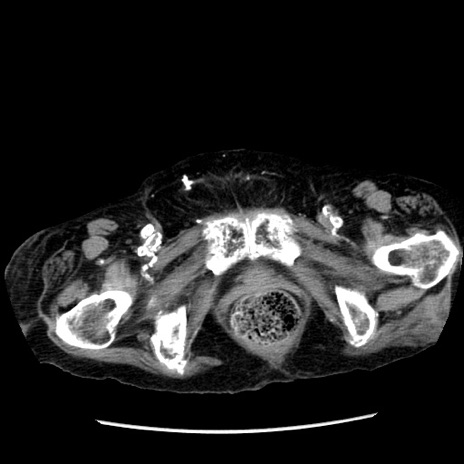

症例14(横断像)

【症例】 90歳代女性

【主訴】 腹痛・嘔吐

【現病歴】今朝から左側腹部痛を認めた。 経過観察していたが、嘔吐を認めたため来院。

【既往歴】 子宮癌術後

【身体所見】 意識清明、BP 127/54mmHg、P 98bpm Sp02 95%(RA)、BT 35.8°C、腹部平坦・軟腸ぜん動音聴取良好、右下腹部圧痛(+) 反跳痛なし

【データ】WBC 9800、CRP 0.46